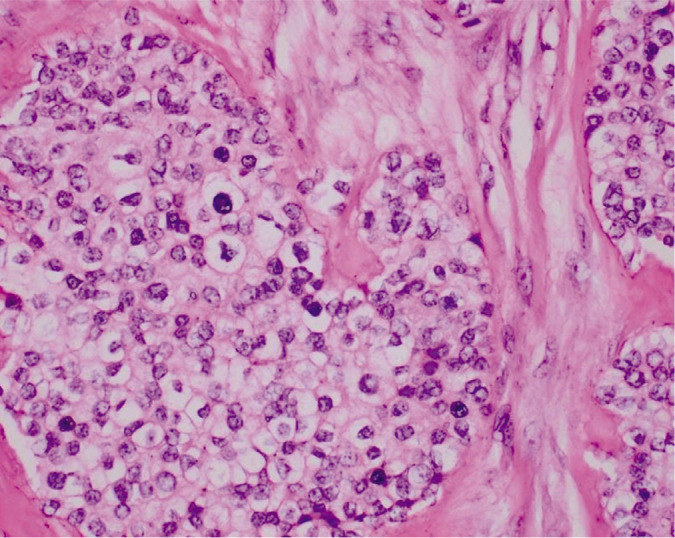

Hyalinizing clear cell carcinoma of the salivary gland is a rare neoplasm, accounting for only less than 1% of malignancies arising from the salivary gland. It is molecularly defined by the expression of the EWSR-ATF1 fusion oncogene. To date, there has been no previous studies published yet in the Philippines regarding the existence of this tumor. In this paper, we present a case of a 70-year-old elderly female who had a 10-year history of a gradually enlarging left lateral neck mass. Histopathologic examination showed a tumor arranged of cords, nests, and trabeculae of monomorphic round cells with abundant clear to lightly eosinophilic cytoplasm surrounded by thick hyalinized collagen bundles. Immunohistochemistry and molecular studies were done which revealed a positive p63 staining, negative SMA and S100, and an EWSR1 rearrangement in Fluorescence in situ hybridization (FISH), thus, confirming the diagnosis.